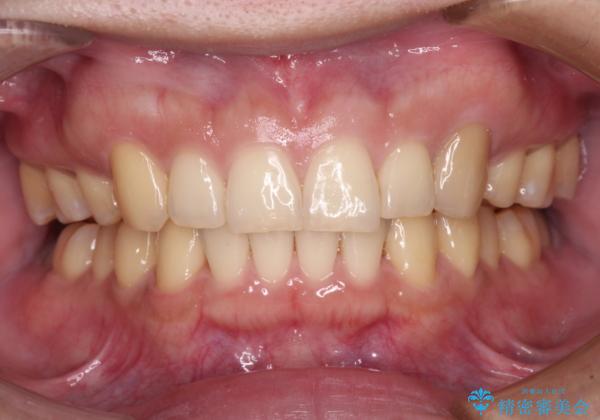

今回の治療では終了時に奥歯は接触しているものの、接触の程度は物足りないものがある状態でした。今後保定期間に少しずつ奥歯の咬合を改善させていくことになります。